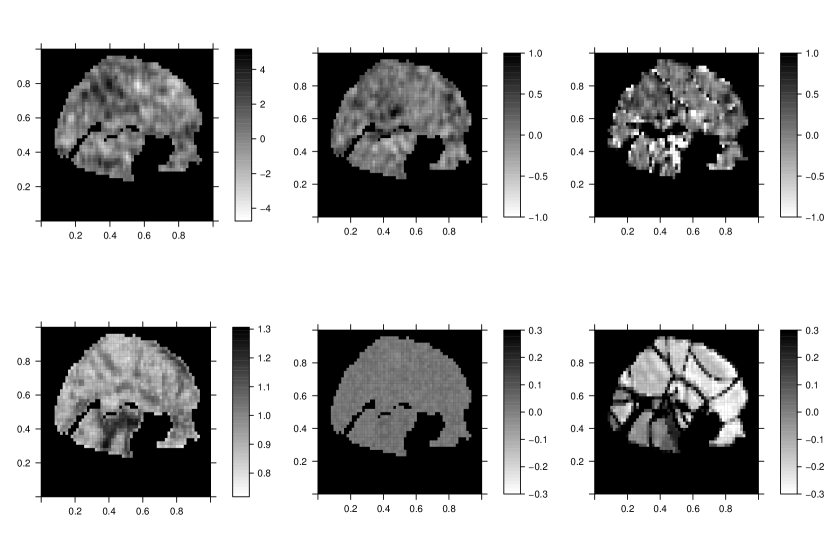

Figure 2 shows the true AR orders, the estimated maximum orders from our SVARO model, and the difference of the two. The estimated maximum orders are obtained by averaging the posterior mean at each voxel over their simulation replicates and rounding. We can see that most of the orders match between the two figures indicating good performance. However, there are some negative values in the difference map.

Next we compare SVARO with PVB and PMCMC in estimating the st AR coefficient. As shown in Figure 3, SVARO shows little error compared with the truth, indicating that our model has captured the autoregressive parameter quite well. In contrast, PMCMC and PVB exhibit more bias, indicating a lack of fit for the temporal noise. Note that we are only displaying the SVARO estimates for the st AR coefficient for simplicity and direct comparison, the other AR coefficients are similarly well-estimated.